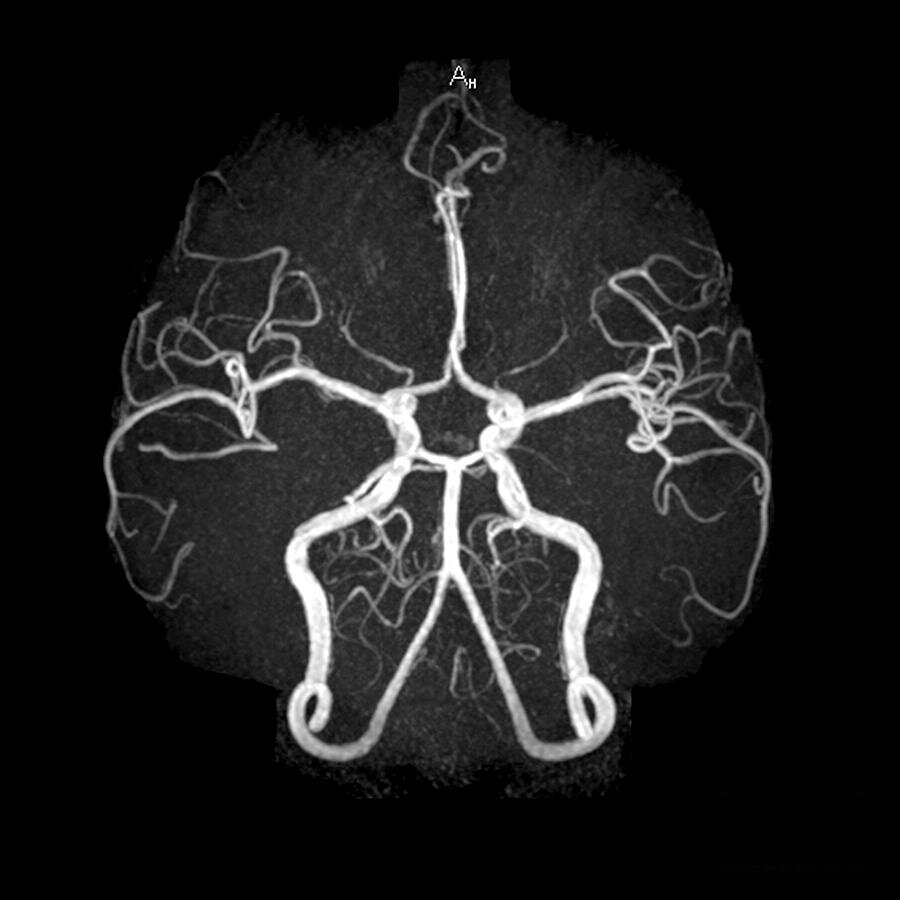

Компьютерная томография сосудов головного мозга или КТ ангиография головного мозга (КТА) – современный вид диагностики с использованием рентгеновских лучей. Благодаря данному методу можно получить послойные снимки исследуемой области организма и затем создать из них трехмерную модель. КТ ангиография артерий головного мозга позволяет проводить точные исследования сосудистой системы и мозгового кровотока абсолютно безболезненно для пациента. Компьютерный томограф делает серию снимков, на которых четко видны сосуды головы и шеи.

КТ сосудов головного мозга с контрастом

КТ ангиография сосудов головного мозга всегда проводится с контрастом. Контраст вводится для прокрашивания просветов артерий и вен. Это позволяет врачам визуализировать сосуды головного мозга диаметром до 1 мм. Без контрастного усиления сосудистая система плохо видна на снимках. Контрастирование при КТ ангиографии головы осуществляют с помощью введения болюсным способом йодсодержащего контрастного препарата из расчета 2 мл на 1 кг массы обследуемого. Для этого в локтевую вену пациента введут специальный катетер. После этого медицинская сестра присоединяет к катетеру автоматический шприц с колбой, наполненной контрастным веществом, и начинает сканирование.